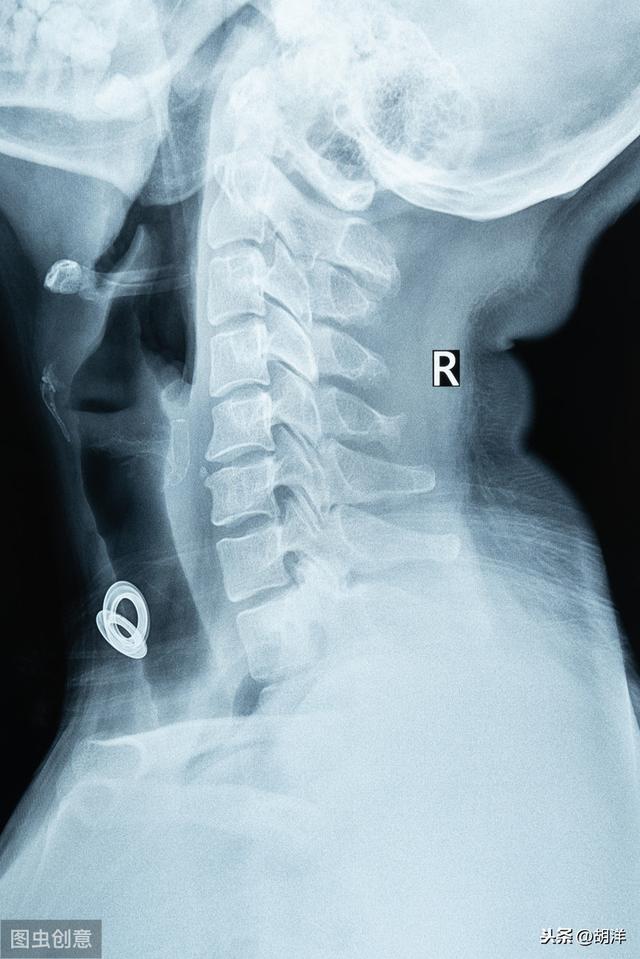

第二に、頚椎症は手のしびれの一般的な原因でもあり、脳の血液供給が不足すると反対側の手足のしびれも生じますので、病院に行って頚椎のフィルムを見て診断を確認することができます。同時に、心血管疾患や脳血管疾患を除外することもできます。

I. 頸椎症

頚椎症は、頚椎椎間板変性疾患、頚椎椎間板ヘルニアまたは頚椎骨棘であり、頚椎椎間孔狭窄に影響を与え、椎間孔は、神経が移動するためのチャネルであり、神経は、椎間孔から手と足の神経の神経支配のうち、調整に到達するために、人体の手足の正常な動きを維持する。

椎間板ヘルニアや骨増殖が神経の通り道を占拠すると、神経、特に後根神経を圧迫し、伝導感覚障害や異常を起こし、手のしびれが生じます。このようなしびれは神経の分布に関係することが多いので、頚椎症の患者さんの中には手足のしびれや異常感覚を訴える人がいますが、これはほとんどが頚椎症性神経根症に関係するものです。

1.頸椎症 手のしびれの最も一般的なタイプは神経根頸椎症で、主に頸椎の突出椎間板過形成骨または石灰化靭帯と椎体圧力の湾曲変化により神経根の上肢に、神経伝導が弱まることになり、明らかな手のしびれの症状が発生します。また、神経根の圧迫が深刻になると、上肢の片側または両側の筋力低下、あるいは筋萎縮を引き起こしやすくなり、患者の生活の質に深刻な影響を与えます。一般的に、頚椎症による手のしびれは片側性に多く見られます。

(2) 頸椎症.頚椎症は手のしびれ疾患の最も一般的な原因であり、頚椎症は上肢の神経が圧迫されると、上肢、腕にしびれや痛みが生じ、頚椎の痛み、ねじれなどの頚椎症の典型的な症状を伴う。

頸椎についてお話ししましょう。

神経原性頚椎症は、軽度であればマッサージなどで痛みを和らげることができますが、普段から水泳など頚椎を動かすことができるスポーツを多く行い、睡眠を適度に取りながら生活し、食事は栄養価の高いものを摂ることをお勧めします。 状況がより深刻であれば、時間内に病院へ行き、病気の原因を突き止め、治療を行うことをお勧めします。

第二に、頚椎症

頚椎症は頚椎過形成を引き起こし、首の血管や神経を圧迫し、手足の機能に影響を与え、程度の差こそあれ手足のしびれを引き起こす。

第三に、頚椎症:頚椎症は中高年によく見られる病気で、手のしびれもその症状の一つである。頚椎症は、理学療法、浮き針、絆創膏、漢方薬の崩れたシミ、血液循環を活性化する薬などで治療することができます。通常、あなたはしばしばいくつかの遅い活動の首の健康体操を行うことができますし、適切な睡眠枕の高さに注意を払う、一般的に7〜9センチメートルの高さ、高すぎず、低すぎず、柔らかく、適度な硬さ、睡眠姿勢を正しくする必要があります、あなたはまた、頸椎症を改善するために大豆枕を行うことができます。